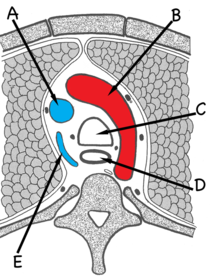

Benævn de markerede strukturer: A: Vena Cava Superior B: Arcus Aortae C: Trachea D: Osophagus E: V. Azygos